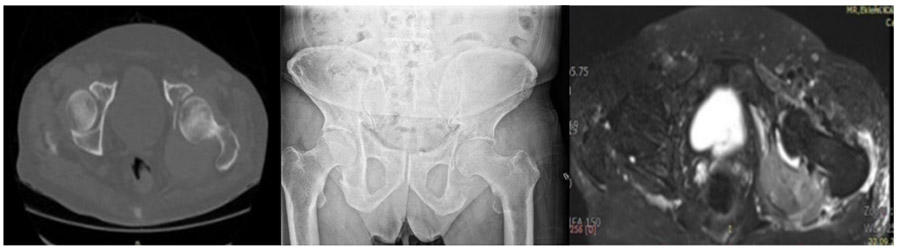

Before the surgery: X-ray, MRI, and CT scans show a mass lesion and significant damage in the posterior aspect of the left hip joint.